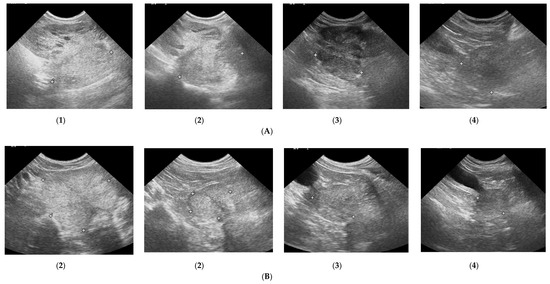

3.1. Prostate B-Mode Appearance